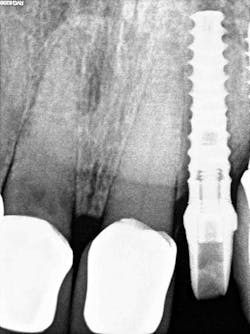

- Radiographic findings: Fractured lateral incisor with periapical pathology

- Implant: Ditron Ultimate 3.75 x 16 mm

- Abutment: Final straight 11.5 mm titanium abutment delivered at time of implant placement